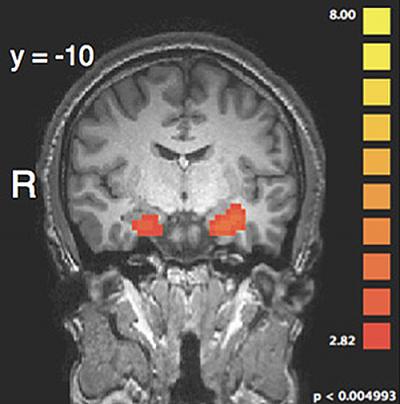

The fMRI scans revealed the areas of the brain that are involved in this complex process. They found that the amygdala, an almond-shaped set of neurons that plays a key role in processing emotions, responded most strongly to the graphic language condition. Like the punishment ratings themselves, however, this effect in the amygdala was only present when harm was done intentionally. Moreover, in this situation the researchers found that the amygdala showed stronger communication with the dorsolateral prefrontal cortex (dlPFC), an area that is critical for punishment decision-making. When the harm was done unintentionally, however, a different regulatory network -- one involved in decoding the mental states of other people -- became more active and appeared to suppress amygdala responses to the graphic language, thereby preventing the amygdala from affecting decision-making areas in dlPFC.